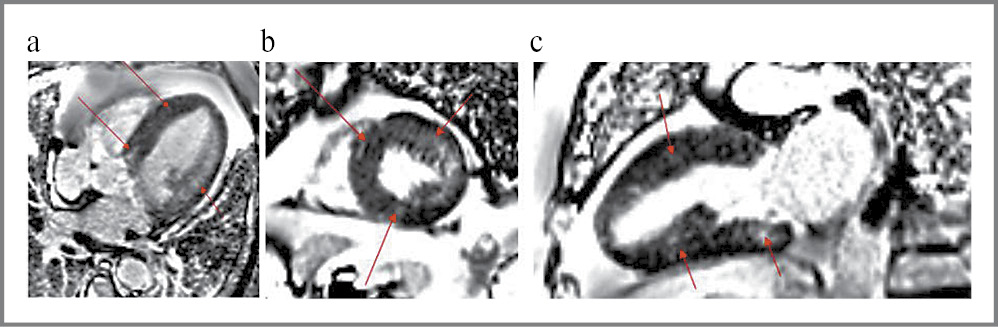

Для уточнения характера поражения миокарда выполнена МРТ сердца с контрастированием, подтверждено выраженное увеличение ММЛЖ. ГЛЖ оказалась более выражена в средних сегментах ЛЖ, достигая максимальных значений до 21 мм в области МЖП. Примечательно, что базальный сегмент МЖП демонстрирует постепенное утолщение с 12 до 21 мм, чем обусловлено отсутствие обструкции выносящего тракта, подтвержденное в режиме кино-МРТ. Также по данным МРТ выявлено увеличение конечно-диастолического объема (КДО) ЛЖ, объема ЛП, однако при пересчете результатов на площадь поверхности тела больного (индексированные объемы) полученные данные соответствовали референсным значениям (табл. 3).

Контрастное исследование выявило интрамиокардиальное накопление препарата по всем стенкам ЛЖ, в большей степени выраженное в максимально гипертрофированных участках миокарда (рис. 8).

Рис. 8. МРТ сердца с контрастированием, стрелками обозначены участки интрамиокардиального фиброза.

Fig. 8. Contrast-enhanced cardiac MRI, arrows indicate areas of intramyocardial fibrosis.